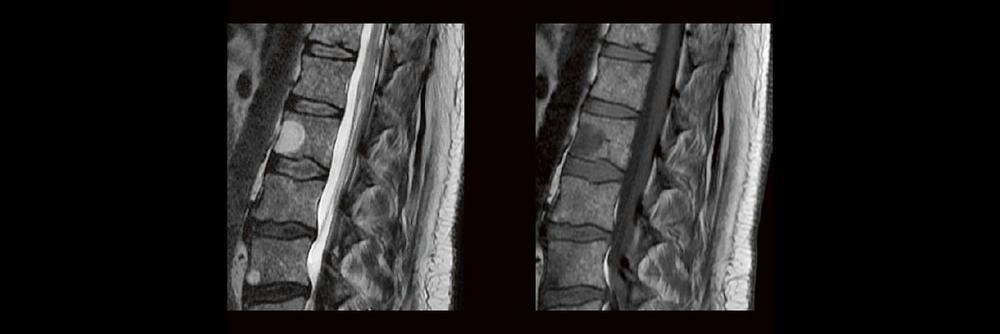

In der täglichen Routine hat man wenig Zeit, sich lange mit den Bildern zu beschäftigen, die man anfertigt. Dennoch soll man auf bestimmte Erkrankungen richtig reagieren und die Protokolle anpassen. MTR´s sind keine Ärzte, dennoch gibt es ein Krankheiten, die eindeutige Bildmerkmale zeigen. In diesem Webinar werden eine Reihe solche Erkrankungen gezeigt. Woran erkennt man einen Schlaganfall, ein Hämagiom, eine Metastase oder Fraktur? Diagnosen die man sehen muss um richtig zu reagieren? – hier werden sie gezeigt.